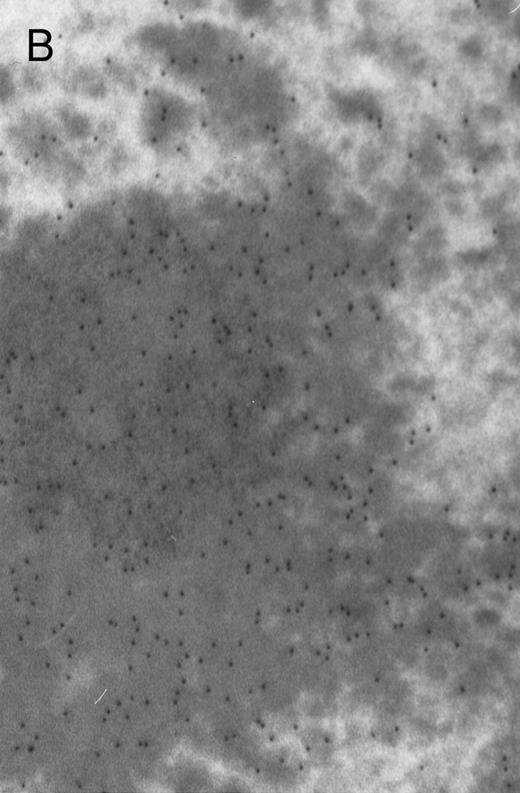

In both cases no. 1 and no. 2, electron microscope studies demonstrated electron-dense inclusions in 30% of early and late polychromatic erythroblast sections and many marrow reticulocytes. In ultrathin sections that reacted with monoclonal antibodies to either α- or β-globin chains followed by gold-labeled anti-mouse IgG, the density of gold particles over the majority of the inclusions was clearly greater than that over surrounding inclusion-free cytoplasm (Fig 3). By contrast, in sections from the two patients with β-thalassemia major, gold particles were concentrated over the inclusions following incubation with the antibody to α-globin chains, but not to β-globin chains (Fig 4A-C). The density of gold particles over inclusions in all control preparations was not greater than that over surrounding cytoplasm (Fig 4D).

Electron micrographs of erythroblastic inclusions from sections of marrow immunogold-labeled with mouse monoclonal antibody. Inclusions from a case of β-thalassemia major show a positive reaction with antibody against human α-globin chains (A, B) and no reaction with antibody against human β-globin chains (C). B shows part of the inclusion in A at higher magnification. There is virtually no labeling of inclusions in a control section that was reacted with normal mouse serum instead of a monoclonal antibody (D). Magnifications: A, × 20,000; B, × 59,000; C, × 23,000; D, × 35,000.

Prominent intra-erythroblastic inclusions were also present in both of these individuals (patients no. 1 and 2) with dominantly inherited β thalassemia. The percentage of polychromatic erythroblast sections containing inclusions in the two cases was 30%, which is considerably above the range (0.2% to 2.8%) previously reported in β-thalassemia trait.13 We have investigated the composition of the inclusions in cases no. 1 and 2 by immunoelectron microscopy using mouse monoclonal antibodies against human α- and β-globin chains and the immunogold technique. The intra-erythroblastic inclusions in the two cases reacted with both monoclonal antibodies to α- and β-globin chains, clearly indicating that these inclusions contained both types of chains. In contrast, the intra-erythroblastic inclusions found in homozygous β thalassemia reacted with the monoclonal antibody against α globin but not β-globin chains, confirming that they consisted only of precipitated α-globin chains. These data support the hypothesis that the cellular pathology underlying the dominantly inherited β thalassemias is related to the synthesis of highly unstable β-globin chains, which are not able to form functional tetramers. These abnormal β-chain variants precipitate intracellularly together with the concomitant excess α-globin chains to form large inclusions, which leads to more severe ineffective erythropoiesis than in heterozygous β thalassemia, in which much smaller amounts of precipitated globin chains are found.17